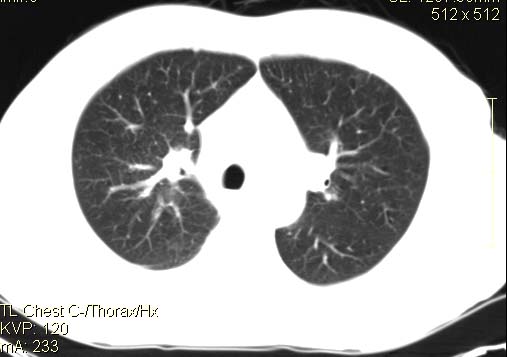

以下是引用qc80012345在2007-4-17 12:33:00的发言:[br]右肺下叶周围型肺癌伴肺门及纵隔内淋巴结转移;比较清楚。

以下是引用qingyuan在2007-4-17 14:19:00的发言:[br]右肺下叶外侧后段胸膜下区节结样病变、分叶、内可见空洞,壁厚薄不均,胸膜凹陷、肺门周围区纹理增粗、僵硬、并近似小结节样改变,肺门区软组织节结、纵膈淋巴结肿大,患者病史长、抗炎治疗无好转炎性改变基本排除,考虑:右肺下叶周围型肺癌伴纵膈及右肺门区淋巴结转移、肺内淋巴管受侵。